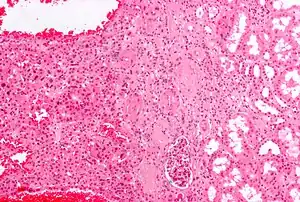

Micrograph of a renal oncocytoma. H&E stain.

An oncocytoma is an epithelial tumor composed of oncocytes, large eosinophilic cells having small, round, benign-appearing nuclei with large nucleoli and excessive amounts of mitochondria.